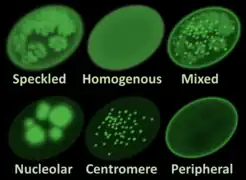

Blood tests can be done to determine if a patient has high levels of antibodies that are indicative of the condition, such as antinuclear antibody (ANA) and rheumatoid factor (because Sjögren's syndrome frequently occurs secondary to rheumatoid arthritis), which are associated with autoimmune diseases. Typical SS ANA patterns are SSA/Ro and SSB/La, of which anti-SSB/La is far more specific; anti-SSA/Ro is associated with numerous other autoimmune conditions, but is often present in SS. However anti-SSA and anti-SSB tests are frequently not positive in SS.